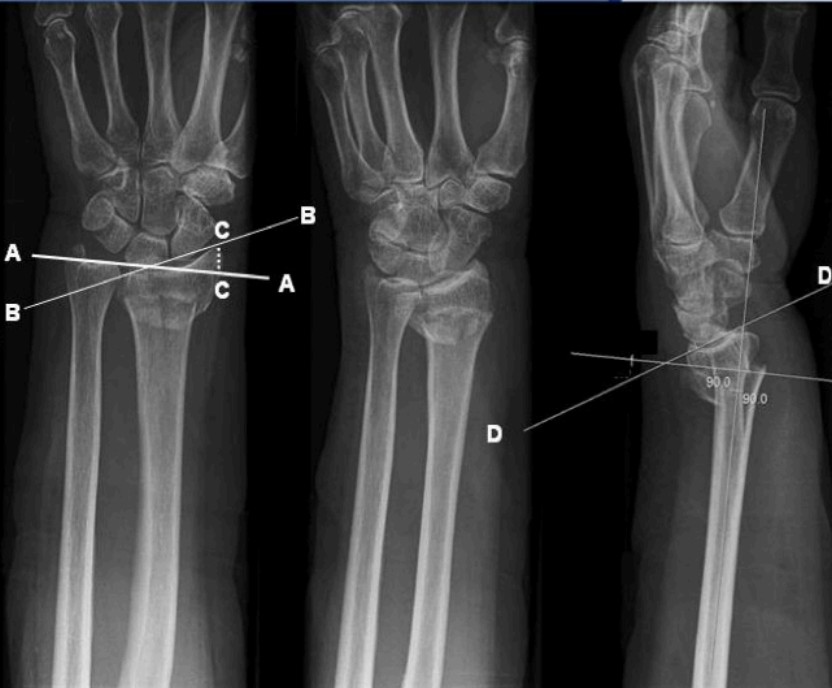

Perilunate wrist dislocation

An 88-year-old man is brought in by ambulance to your emergency department atier a fall down 3 steps onto his …